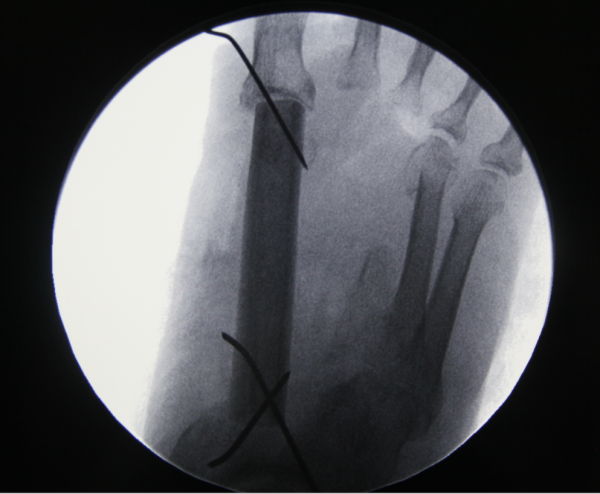

玉米机伤右足复合组织缺损,腓骨皮瓣修复,术后12天,伤口愈合良好,今日出院清创后

x线